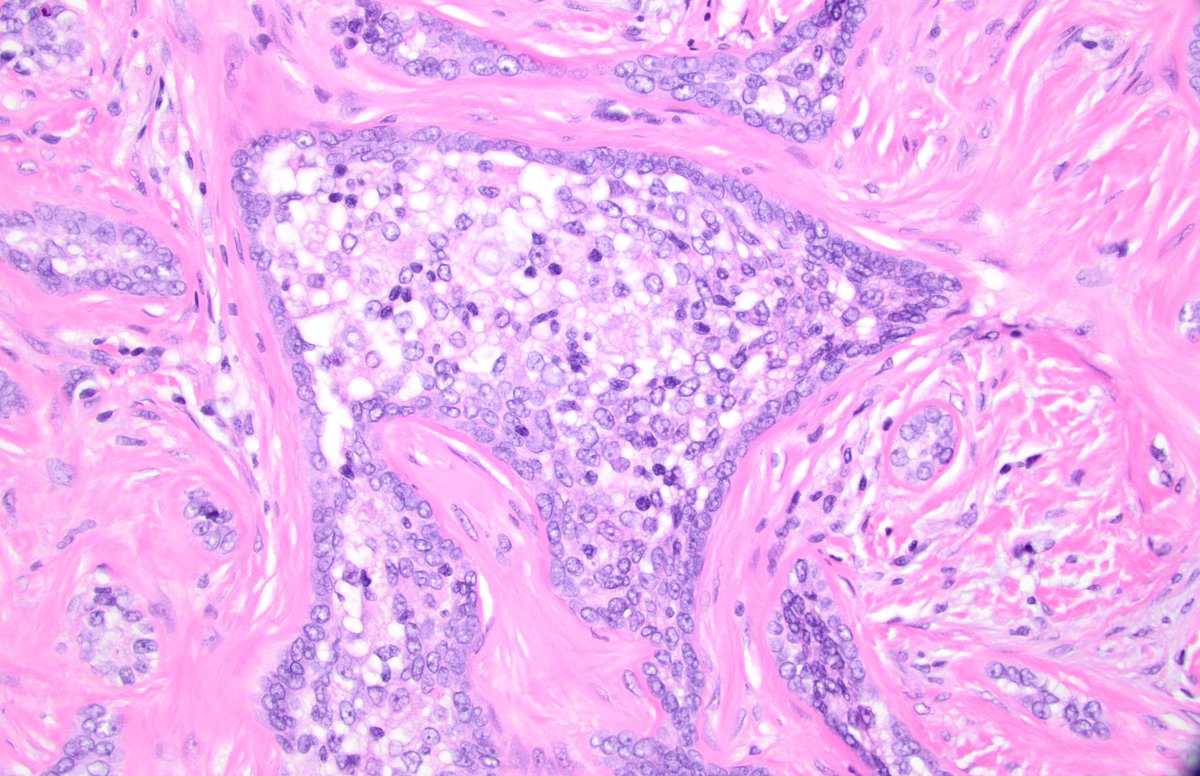

#GUpath 60s M, h/o clear cell RCC with met to LN, now presents with adrenal gland mass, adrenalectomy performed can you provide explanation for🔬? #pathstories